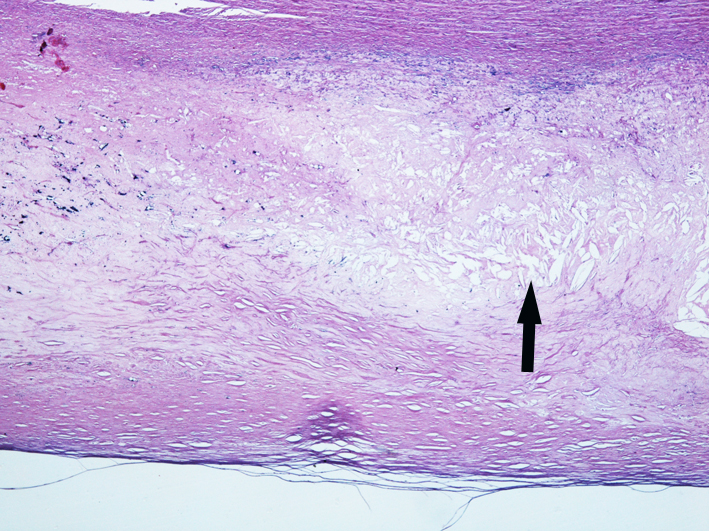

4.Atherosclerosis of aorta